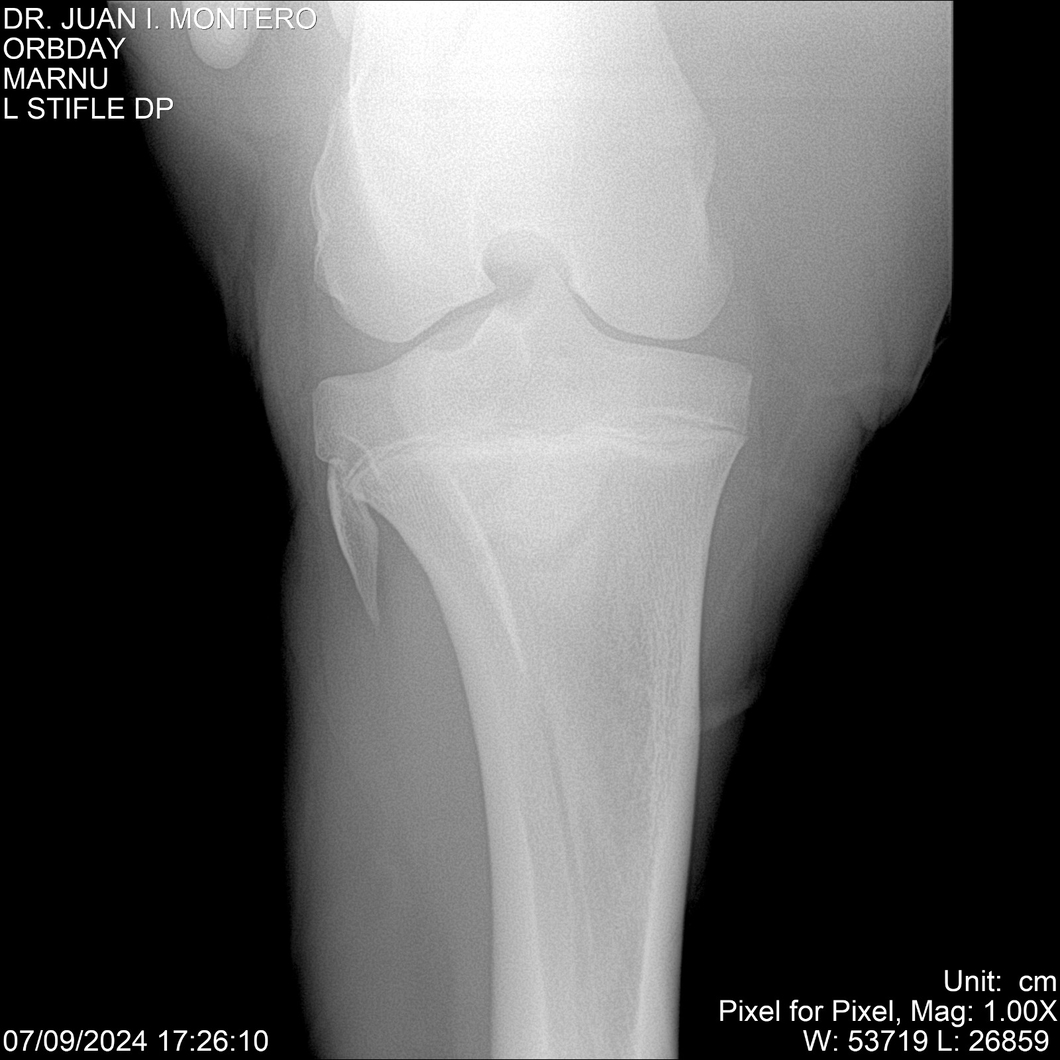

• Empresa: Abelenda N. R., Walter Hugo